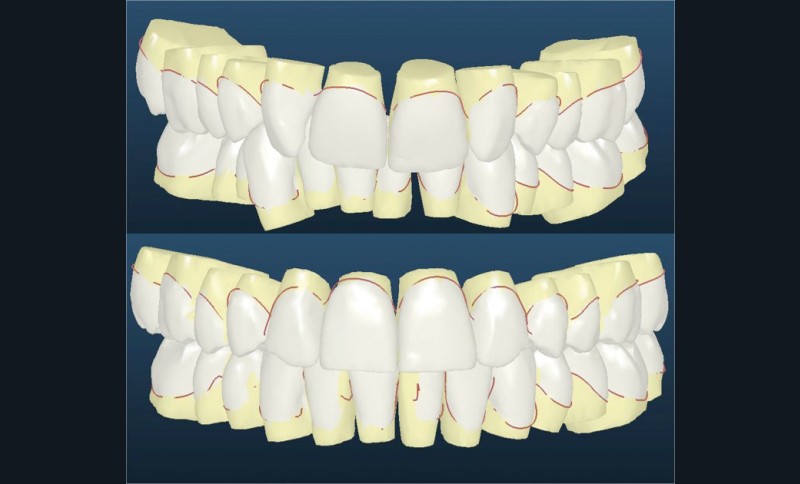

Nous lui avons donc proposé un traitement d’alignement avec maintien des 14 et 24 en position de 13 et 23 et optimisation du torque pour favoriser un développement des arcades et chercher à améliorer le sourire et le soutien labial.

La patiente donne son accord pour un appareillage Damon Insignia métal qui permet une individualisation complète des brackets dans les 3 sens de l’espace.

Un appareillage Damon métal a été mis en place, réalisé à partir d’un set up numérique Insignia pour obtenir un contrôle précis des torques et de la forme d’arcade et réduire le temps de finition grâce à un collage indirect très précis.